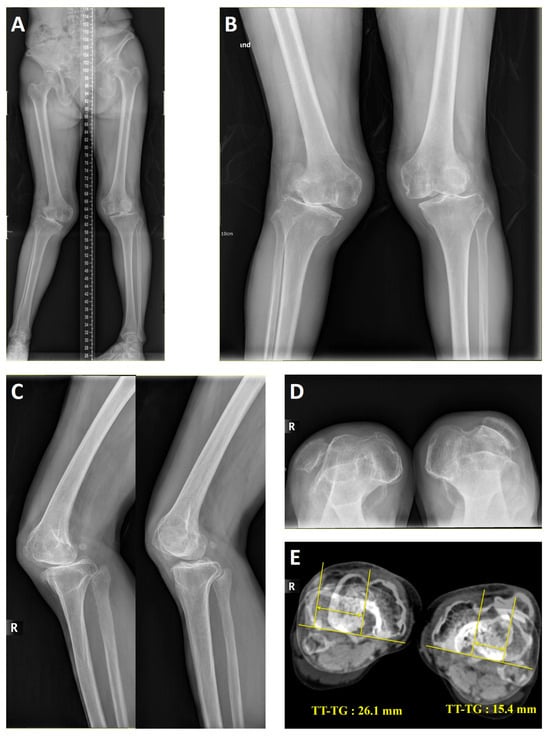

| 1 | F/68 | Left | 2.3 | + | + | + | 15.4 | +/16 | + | + | ||||

| 2 | F/68 | Right | 20.8 | + | + | + | + | 26.1 | −/18 | + | + | + | + | VY-Q |